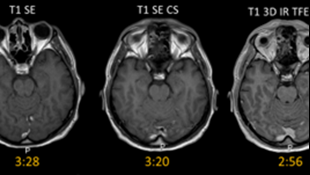

A new generation of MR pulse sequence technology has arrived. The techniques are collectively known as advanced acceleration technology or AAT. AAT promises to deliver MR imaging faster than ever before, which can have a significant impact on how MR departments are run whilst benefitting patients, radiologists, radiographers and waiting lists if deployed to its full potential. However, there is no standard way of deploying this complex technology across the full range of MR scanner protocols and manufacturers, and it was quickly realised that guidance and shared experience from early adopters of the technology would add benefit to other MR services new to AAT.